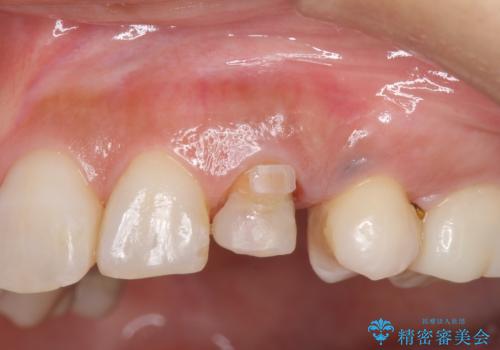

終了時

左:虫歯を除去したところ。遠心が歯ぐきより深い状態です。中:そのままかぶせようとすると、遠心が歯ぐきが腫れやすい状態です。右:エクストリュージョンをしたことで、遠心の歯ぐきの腫れが収まっていることがわかります。

術後は計画通り歯ぐきの腫れが収まり、炎症に強い歯ぐきになりました。

歯の変色もあるため、最終的にはクラウンとしました。